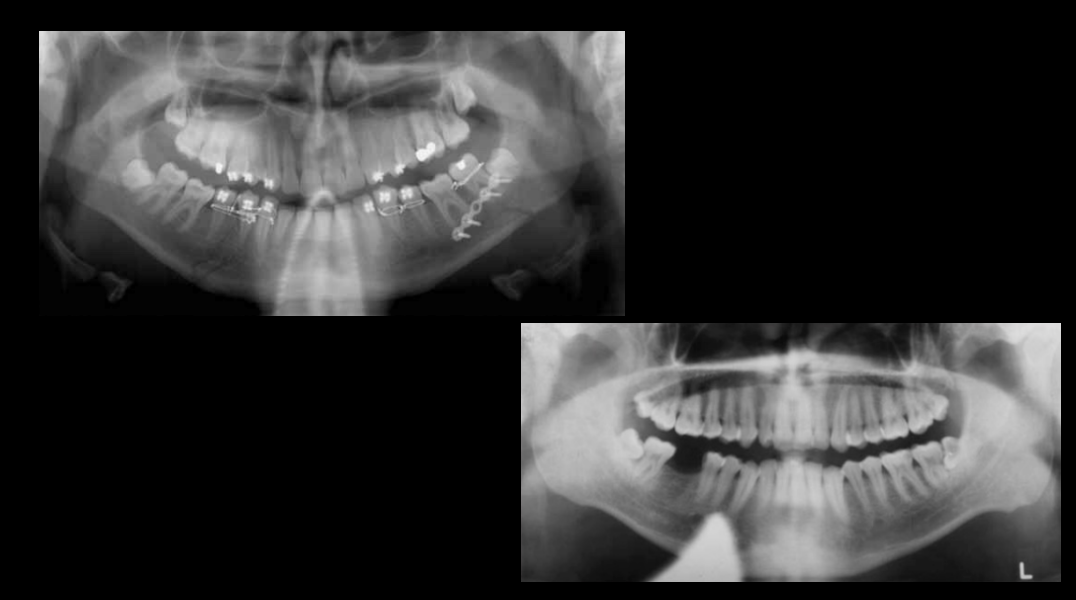

What error is this?

Error: patient too far foward

Error: patient too far back

What errors are these?

Error: slumped position/vertical spine shadow